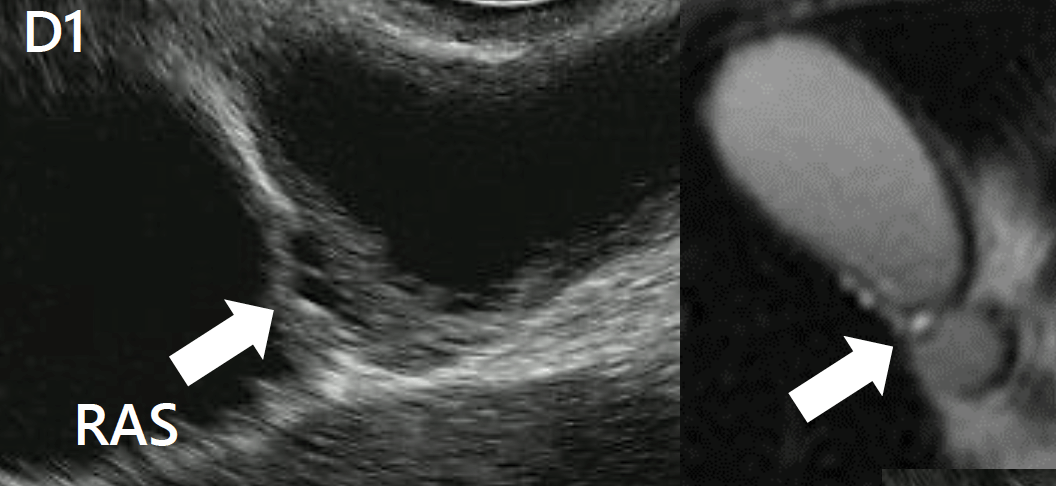

Los signos sugestivos incluyen engrosamiento de la pared, contenido luminal anecoico o ecogénico (lodo biliar, cálculos), imágenes pseudocísticas en la pared correspondientes a los senos de Rokitansky-Aschoff y artefactos de reverberación acústica (“cola de cometa”) debido a concreciones de calcio atrapadas en los RAS.

La ecografía endoscópica mejora la sensibilidad de la ecografía transabdominal, especialmente para el diagnóstico diferencial con cáncer de vesícula biliar.

Engrosamiento segmentario hipoecoico en el fondo de la vesícula biliar, de 11×5 mm, sugestivo de adenomiomatosis. Imagen cedida por la Dra. Julia Mayumi Gregorio.

El signo de “collar de perlas” se refiere a la disposición curvilínea característica de múltiples cavidades intramurales redondeadas e hiperintensas visualizadas en imágenes ponderadas en T2